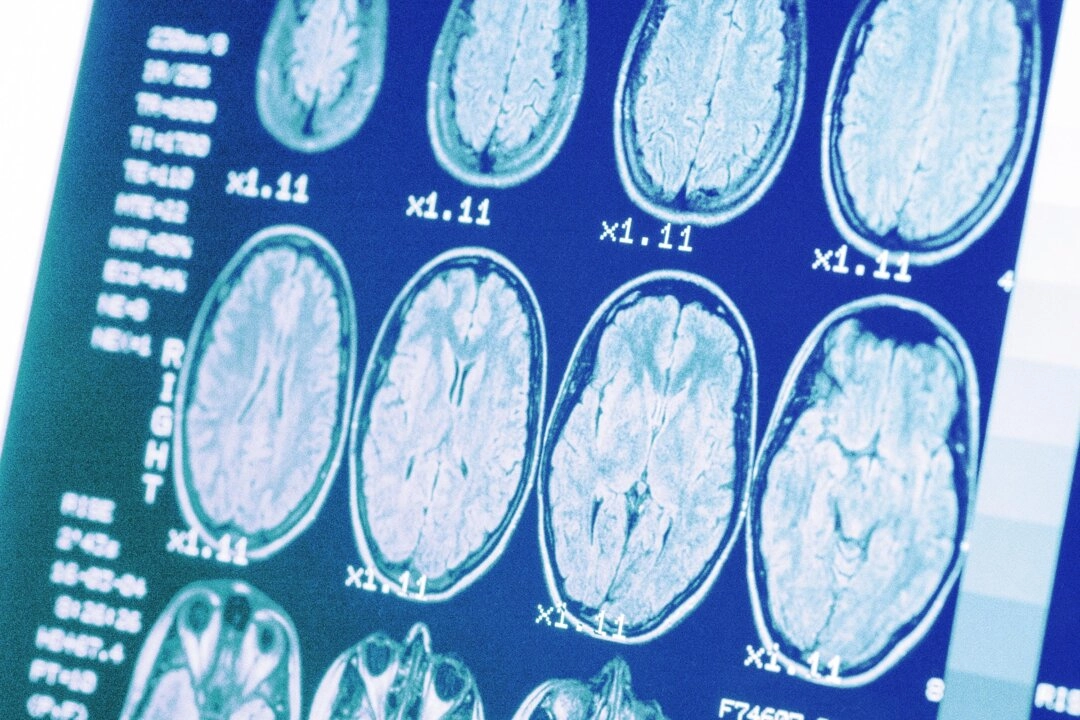

一直到最近,大家才稍微了解淋巴系統在神經健康中扮演的角色。美國羅徹斯特大學醫學中心的丹麥科學家梅肯.內德加德(Maiken Nedergaard)就觀察到一個奇特的現象,她發現大腦中的淋巴管網絡會利用腦脊髓液清除毒素。梅肯把這套大腦淋巴系統命名為「膠淋巴系統」(glymphatic system),因為它必須仰賴腦中的神經膠細胞的協助。2012年,《科學轉化醫學》(Science Translational Medicine)發表了她的研究。除此之外,她的這項研究還有一個非常重要的發現,那就是膠淋巴系統的主要運作時機是落在我們睡覺的時候(這再次強調了一夜好眠的重要性)。

簡單來說,膠淋巴系統就像你大腦的夜間澡堂。它會利用動脈不斷脈動的能量,去交換和引流腦中的廢物(例如代謝物和蛋白質),並與大腦的淋巴系統相連,將這些廢物排出體外。你在睡覺的時候,它清除這些廢物的速度是你清醒時的兩倍快,這或許就是我們不規律睡覺,就無法好好生存的原因。這些結果也讓我們有了一套新假設,去解釋「為甚麼我們一定要睡覺」這個古老的問題。

膠淋巴系統受到限制時,它就會很難修復腦中的損傷和清除累積的毒素。科學家就發現,認知障礙症和阿茲海默症患者的大腦會堆積大量的類澱粉蛋白斑塊(amyloid plaques)。大腦免疫學暨神經膠質中心(Center for Brain Immunology and Glia,BIG)在美國聖路易斯華盛頓大學醫學院(Washington University in St. Louis School of Medicine)由喬納森.基普尼斯(Jonathan Kipnis)領導的研究團隊,就是在探討老化是如何影響這些膠淋巴管的機能。

隨著我們的年歲漸漸增長,這些位處大腦的微小淋巴管也會漸漸變窄,越來越難把廢物帶出大腦。這個研究團隊發現,中樞神經系統的腦膜淋巴管不通暢時,會導致認知受損。於是他們做了一項實驗,利用一種特殊蛋白當作生長因子,增加受試者的淋巴管管徑。他們的實驗結果顯示,淋巴管的管徑增加時,受試者不只膠淋巴的循環會變好,就連學習力和記憶力等認知能力也會有所改善。